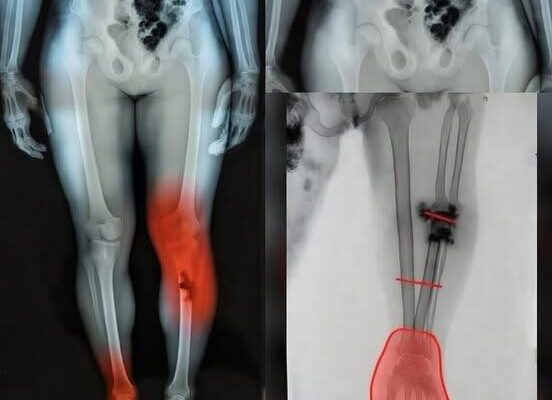

Legendary Spanish Matador Reveals Details of Severe Bullring Injury After Dangerous Goring Incident, Speaking About the Physical and Emotional Impact of One of the Most Challenging Moments of His Career, Highlighting the Risks of Bullfighting, the Intense Demands of the Sport, and the Recovery Process That Followed His Life-Threatening Experience in the Arena

A veteran Spanish matador, Morante de la Puebla, was seriously injured during a bullfight in Seville at the Maestranza arena. The incident occurred in the final stages of his performance when he was caught by a charging bull and suffered significant lower-body injuries. He was quickly assisted out of the ring and taken for emergency…